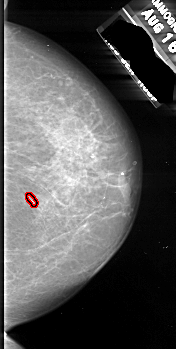

A_1085_1.LEFT_CC

LEFT_CC LINES 5881 PIXELS_PER_LINE 3016 BITS_PER_PIXEL 16 RESOLUTION 42 NON_OVERLAY

FILE: A_1085_1.RIGHT_CC.OVERLAY

TOTAL_ABNORMALITIES 1

ABNORMALITY 1

LESION_TYPE CALCIFICATION TYPE ROUND_AND_REGULAR DISTRIBUTION CLUSTERED

ASSESSMENT 4

SUBTLETY 4

PATHOLOGY MALIGNANT

TOTAL_OUTLINES 1

BOUNDARY